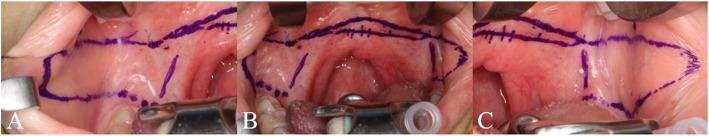

A 14-year-old female with a bilateral complete cleft lip and palate underwent primary cheiloplasty at 3 months and palatorrhaphy at 9 months of age. Despite 10 years of speech therapy and 4 years of speech aid use, hypernasality persisted. To address this, palatal lengthening was performed using bilateral buccinator myomucosal flaps combined with buccal fat flaps. At 1 month postoperatively, partial necrosis of the buccal fat grafts was observed but healed without further complications. At 8 months postoperatively, soft palate elongation exceeding 1 cm was achieved, and nasometric assessments demonstrated nasality reductions of 25.5 percentage points for high vowels (/i/, /wi/) and 19.5 percentage points at the sentence level. In the consonant accuracy evaluation, the patient's word-level accuracy increased from 72.09% preoperatively to 88.37% at 6 months postoperatively. These objective improvements correlated with subjective reports of improved speech and reduced vocal effort.

一名14岁双侧完全性唇腭裂女性患者,3个月时接受了一期唇裂修复术,9个月时接受了腭裂修复术。尽管进行了10年的言语治疗和4年的助音器使用,鼻音过重问题仍然存在。为解决此问题,采用双侧颊肌黏膜瓣联合颊脂瓣进行腭部延长术。术后1个月,观察到颊脂瓣部分坏死,但愈合良好,未出现进一步并发症。术后8个月,软腭延长超过1厘米,鼻音测量评估显示高元音(/i/,/wi/)鼻音降低25.5个百分点,句子水平鼻音降低19.5个百分点。在辅音准确性评估中,患者单词水平的准确性从术前的72.09%提高到术后6个月的88.37%。这些客观改善与言语改善和发声努力减少的主观报告相关。